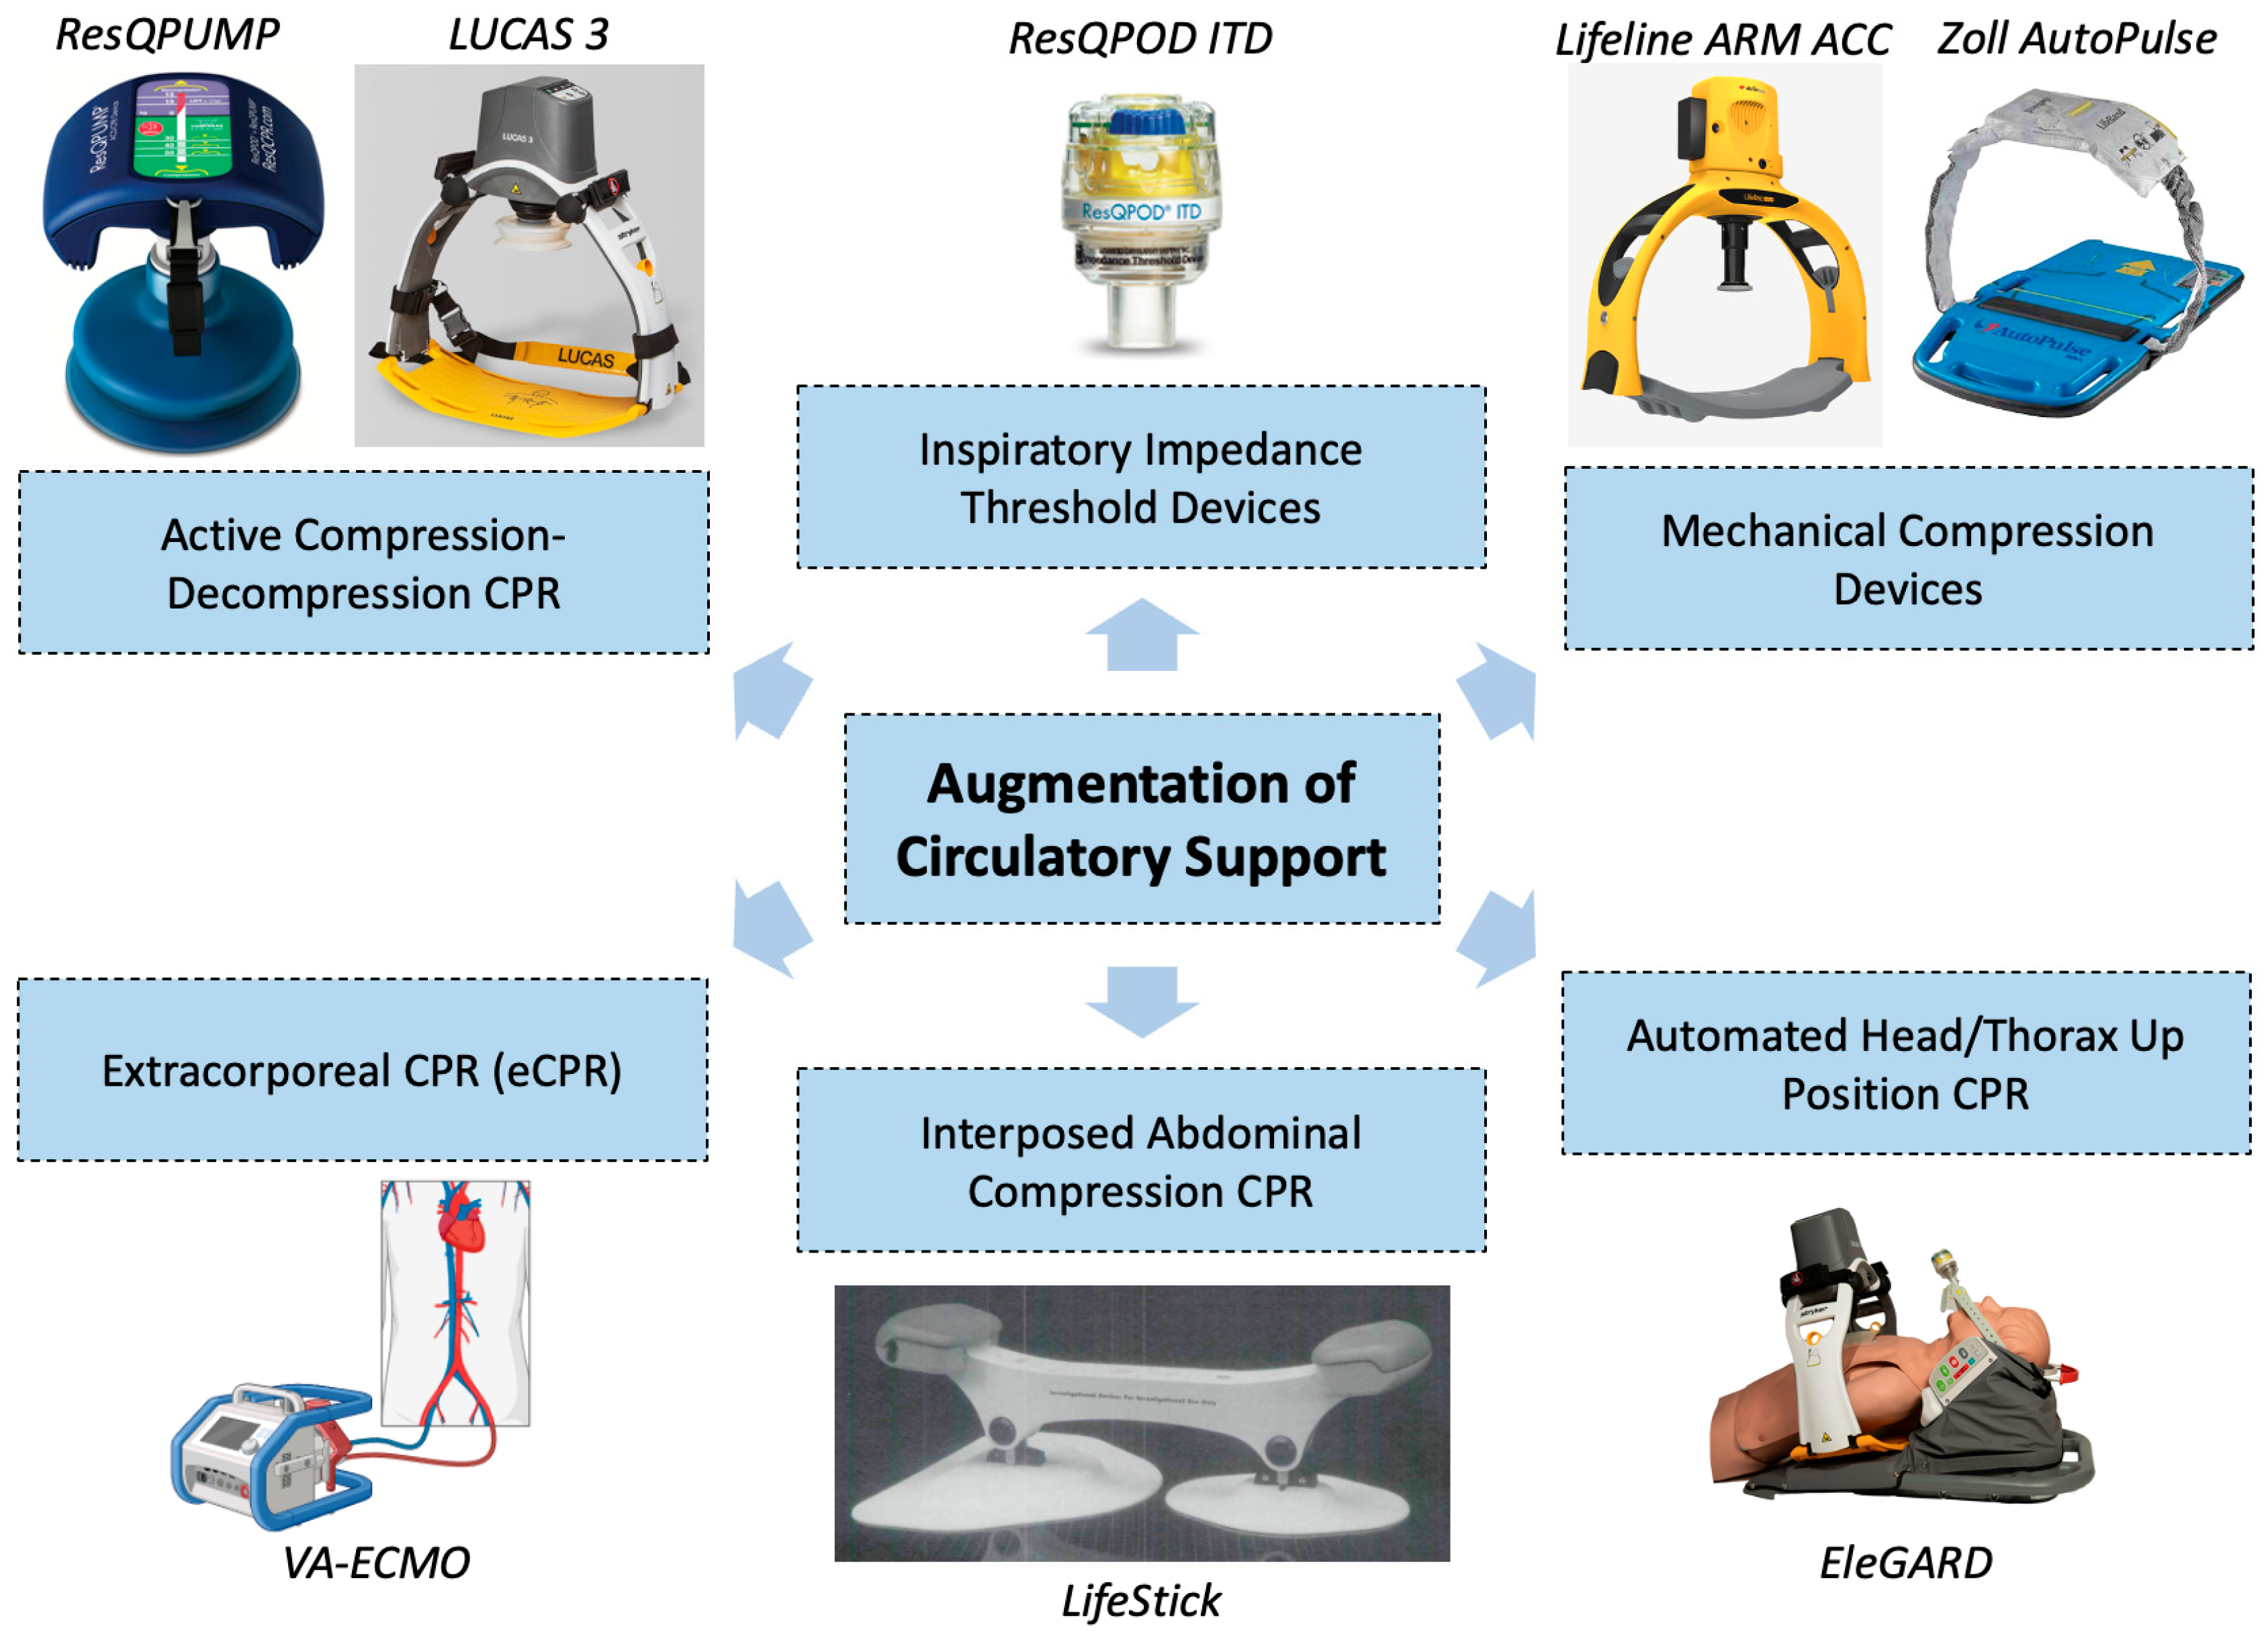

5. Augmentation of Circulatory Support

5.2. Active Compression–Decompression CPR

5.3. Mechanical Compression Devices

5.4. Inspiratory Impedance Threshold Devices

5.5. Interposed Abdominal Compression CPR

5.6. Automated Head/Thorax-Up Positioning CPR

5.7. Extracorporeal Cardiopulmonary Resuscitation (eCPR)